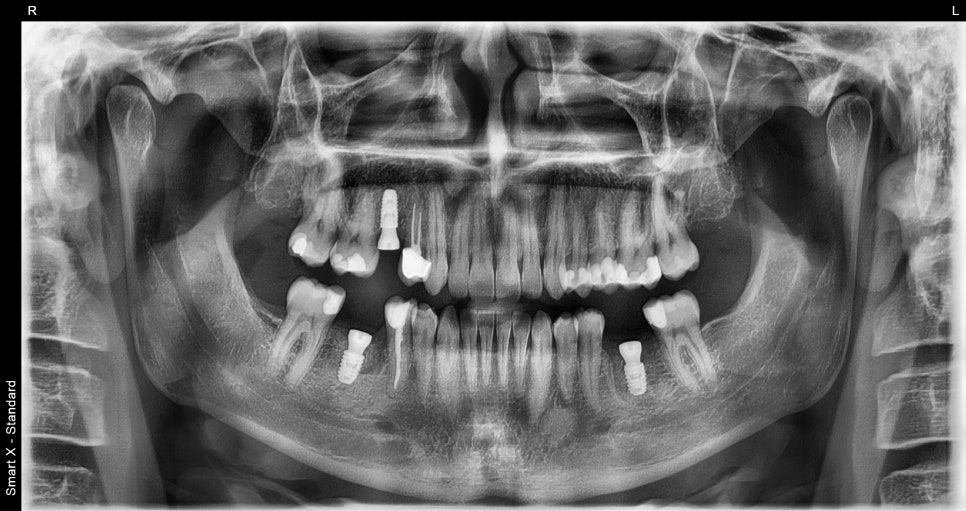

This is the panoramic X-ray taken after implant placement.

The implants were placed neatly and in alignment, just like the adjacent teeth.

This is the final panoramic X-ray after the implants had stably integrated and the prosthetics were successfully placed.

This is the oral condition after completion of both implant, crown, and resin treatments.

Both function and aesthetics were restored satisfactorily.